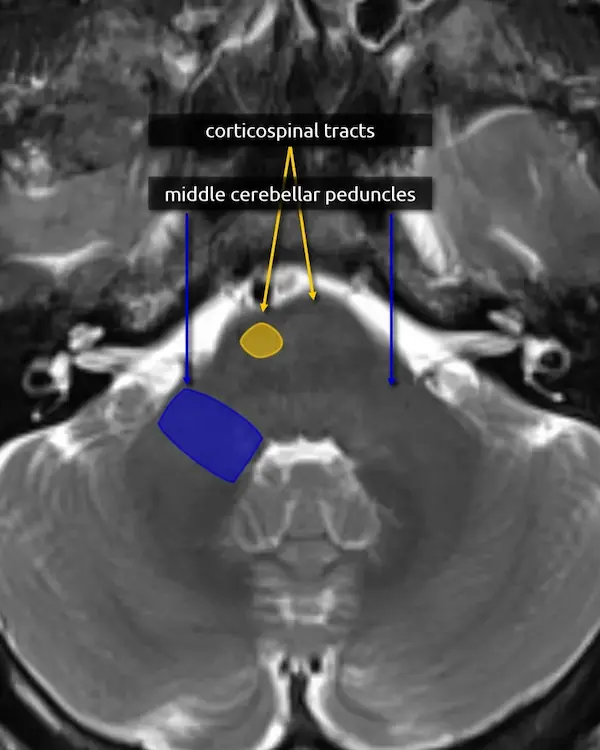

3. Corticospinal tracts

The corticospinal, corticobulbar, and corticopontocerebellar tracts continue inferiorly from the cerebral peduncles.

Lesions of the corticospinal tracts will cause motor deficits of the body and limbs. Sparing or involvement of the corticospinal tracts is a characteristic finding of several conditions, e.g., sparing of the corticospinal tracts is responsible for the "trident sign" of osmotic demyelination syndrome. The corticobulbar tract is located along the medial aspect and can be selectively damaged at this level, producing facial weakness.

1. Corticospinal tracts

2. Superior cerebellar peduncles

3. Middle cerebellar peduncles:

The middle cerebellar peduncles are the largest of the cerebellar peduncles and connect the cerebellum to the pons. The fibers are entirely afferent, originating from contralateral pontine nuclei and terminating in the cerebellum. Over 90% of the fibers in the middle cerebellar peduncles belong to the corticopontocerebellar pathway (see below).

There are many causes of middle cerebellar peduncle signal abnormality, usually resulting from conditions that can cause white matter edema, degeneration, or gliosis. Bilateral T2 hyperintensity of the middle cerebellar peduncles is a classic but not specific sign of fragile X-associated tremor/ataxia syndrome (FXTAS). Multiple system atrophy cerebellar type (MSA-C) and spinocerebellar ataxia are other classic causes of middle cerebellar peduncle atrophy and signal abnormalities.

4. Transverse pontine fibers:

The transverse pontine fibers form the bulk of the mid pons and are crossing white matter tracts that go to, or come from, the cerebellum via the middle cerebellar peduncles. The majority of the fibers belong to the corticopontocerebellar pathway, which is crucial for motor coordination and learning.

A lesion that involves the transverse pontine fibers is likely to produce ataxia.

2. Middle cerebellar peduncles